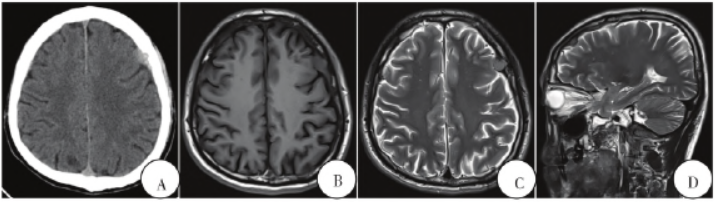

胸腹部影像检查未见明显异常。颅脑CT、MRI提示双侧额部颅骨硬脑膜多发结节样占位,硬脑膜异常增厚,局部颅骨受侵蚀破坏(图1A—G)。影像学诊断:术前考虑硬脑膜转移瘤可能性大。

图1 术前颅脑影像学表现与病理学表现。A:颅脑CT轴位脑窗像示两额部颅骨内板下类梭形稍高密度影,邻近部分颅骨受侵蚀;B—D:颅脑MRI轴位T1、T2WI、矢状位T1WI示两侧额部颅骨内板下方多发结节状改变,两侧额颞部硬膜增厚。E-G:颅脑MRI轴位、矢状位、冠状位增强扫描示硬脑膜增厚局部呈多发结节状改变,呈明显强化,邻近颅骨受累;H:病理表现(HE染色,×100)。